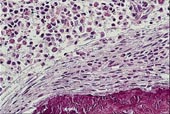

Ved beinaffeksjon utvikler 60 – 70 % radiologisk påvisbare lesjoner. Skjelettforandringene kan være forårsaket av mediatorsubstanser (13). Beinmargen er det hyppigst affiserte organ, bortsett fra hud. Det sees to forskjellige former av mastcelleinfiltrasjon: fokale mastcelleaggregater eller mer diffust utbredte mastcelleinfiltrater, ofte med økt granulopoese og eventuelt andre hematologiske forandringer. De fokale mastcelleaggregatene finnes ofte paratrabekulært med fibrose og eosinofile celler (fig 1a). Mastcellene er som regel atypiske, spolformede og fibroblastliknende, med få og små granulae (14, 15). Fibrosen kan være årsak til tørt aspirat. I perifert blod påvises ofte anemi, 30 % har leukocytose, 25 % trombocytopeni, 25 % eosinofili og 15 % har leukopeni og nøytropeni (15, 16). Eosinofili skyldes sannsynligens produksjon av interleukin 3 og 5 og granulocytt-makrofag-kolonistimulerende faktor i mastcellene (17). Perifer lymfeknutesvulst forekommer hos 25 % og sentral lymfeknutesvulst hos 20 % (15). I leveren sees mastcelleinfiltrater overveiende i portalfeltene (18) (fig 1c). Splenomegali finnes hos 50 – 70 % (17, 19). 35 – 80 % har abdominalsmerter. Hypersekresjon av syre pga. histaminfrigjøring kan gi dyspepsi og smerter i øvre abdominalhalvdel. Smerter i nedre abdominalhalvdel uten symptomlindring av H2-blokker kan kanskje skyldes ødem eller urticaria i gastrointestinaltractus. Diaré sees hyppig, mens malabsorpsjon er sjeldent. Ved malabsorpsjon er det mastcelleinfiltrasjon i lamina propria i tynntarmen (13, 19, 20).

Diagnosen mastocytose stilles først og fremst på grunnlag av histologiske funn i biopsier fra hud og beinmarg, sammen med sykehistorie og kliniske funn. Leverbiopsi og måling av histaminmetabolitter i urin kan være til hjelp. Beinmargsaspirat er som oftest normalt (pasient 2), og inneholder få og normale mastceller. Beinmargsbiopsi er derfor sentralt i diagnostikken av systemisk mastocytose, spesielt når det ikke er hudsymptomer eller objektive funn til stede. Når det gjelder biopsier, er fargemetoden viktig for å påvise mastceller. Farging for tryptase i sekretoriske granulae som er spesifikke for mastceller, er den viktigste (fig 1b). Ved farging med giemsa og toluidinblått kan man demonstrere de metakromatiske mastceller (fig 1c), men basofile leukocytter kan også utvise metakromasi. Da kan immunhistokjemi med monoklonale antistoffer være avklarende. c-kit (CD117) er spesifikk for mastceller, mens laktosylceramid (CDw17) og α -reseptor for interleukin 3 (CD123) er spesifikk for basofile leukocytter (5).